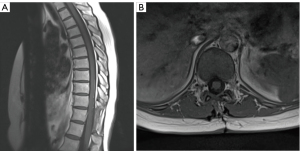

The author immediately ordered a thoracic lumbar spine MRI which revealed an intradural extramedullary circumcised oval-shaped mass measuring approximately 1.9 cm × 0.8 cm × 0.5 cm, as shown in Figure 1A,1B at T11-T12 with enhancement. The spinal MR angiography was performed to rule out a variant arterial malformation such as AV fistula. The test was concluded negative.